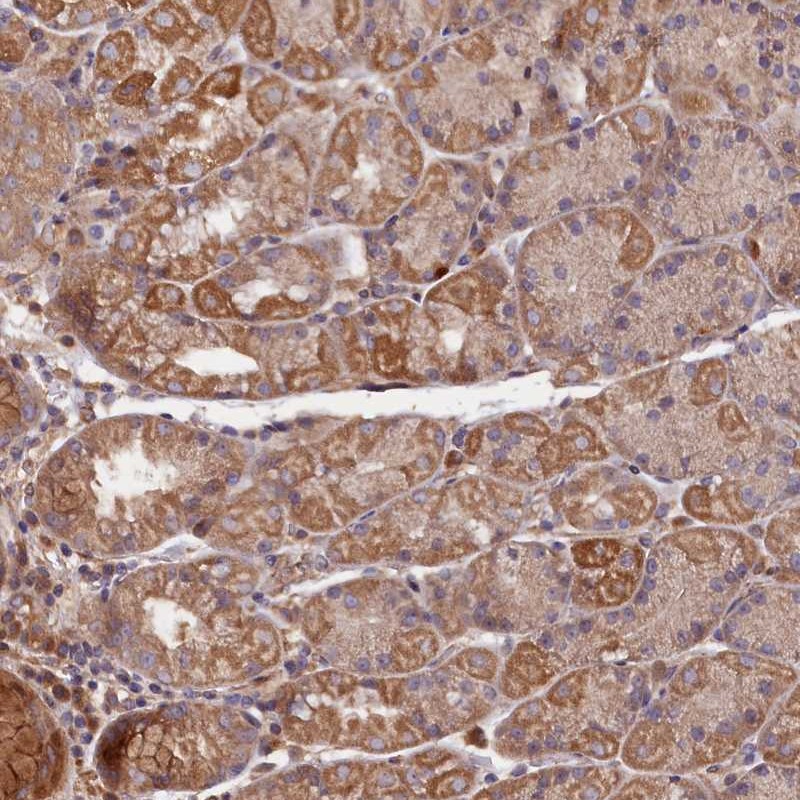

Immunohistochemical staining of human stomach, lower shows moderate cytoplasmic positivity in glandular cells.